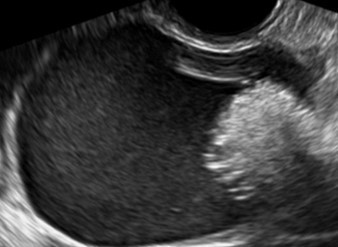

27 yoF with history of prior pelvic surgery

peritoneal inclusion cyst

occur almost exclusively in premenopausal women with active ovaries, pelvic adhesions, and impaired absorption of peritoneal fluid which leads to formatio of fluid filled cysts tha conform to the shape of the peritoneal cavity